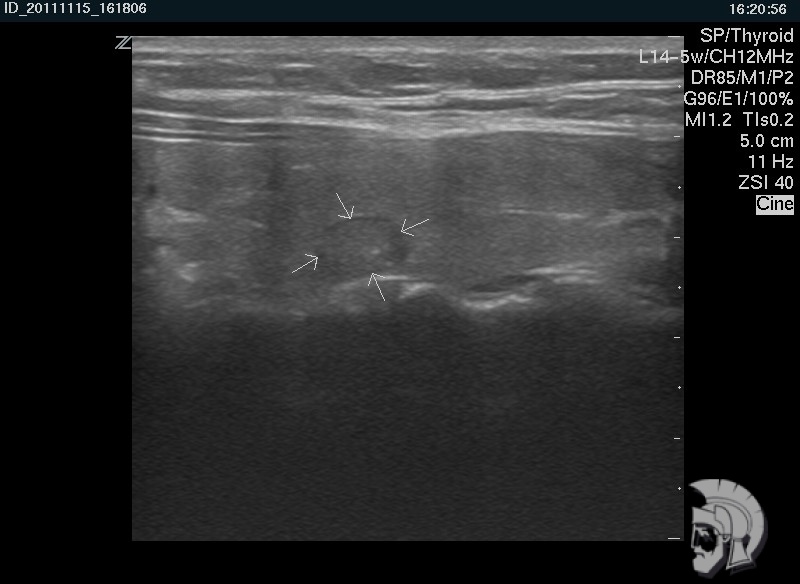

| Фото правостороннего узлового зоба. Тот же случай |

|